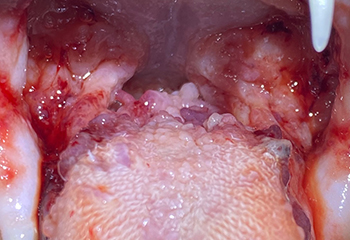

구내염 치료 사례

치료 전

치료 전

치료 전

치료 후(앞니 후방 전발치)

치료 후(전방/후방 전발치)

치료 후(후방 전발치)